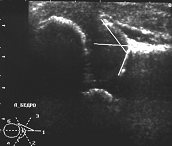

При нарушении центрации сустава и структурного состояния его субхондрального слоя у 4-месячного ребенка при сканировании по методике Графа ядро головки визуализировалось в виде глыбок различной эхоплотности, расположенных выше уровня контура вертлужной впадины (вывих бедра - рис.2).

Рис.2. Сонограмма децентрированного сустава - (вывих) с наличием структурных нарушений гиалинового хряща у 4 -месячного ребенка (сканирование по методике Графа)